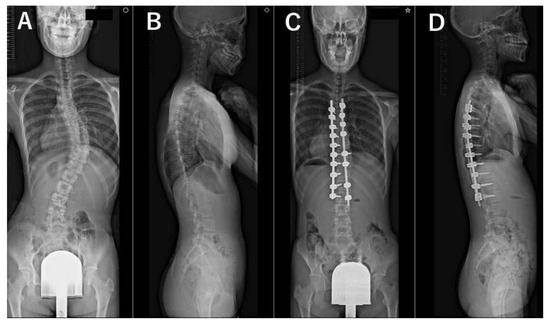

2. Materials and Methods

3. Results

3.3. Radiographic Evaluations